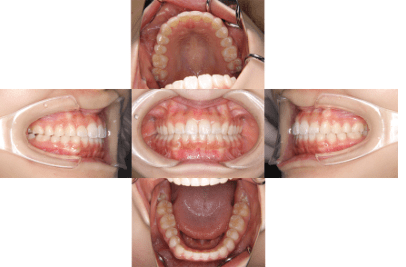

治療後

• 初診時年齢:16歳

• 主訴:叢生

• 診断:叢生を伴う骨格性I級症例、非抜歯

• 治療内容:顎が狭く、上の前歯が後ろに生えてしまい、ガタガタして上手く咬めない状態でした。幅を広くして、歯の角度を調整し、自然な位置に並べたので上手く咬めるようになりました。

• 治療期間:2年

• リスク:ブラックトライアングル(歯と歯の間と歯ぐきの間の三角形の隙間)が強くでる場合がある

• 費用:90万円